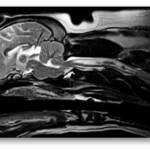

Exceptional Spinal Cord Imaging

The next generation Magnus AIP Vet-MRI veterinary MRI system was designed exclusively for animals.  The system utilizes our novel magnet design providing superior field homogeneity, large 16" field of view and excellent patient access. Our user friendly veterinary specific software includes optimized protocols for each anatomical site and allows maximum flexibility in customizing clinical protocols and post imaging processing.  The wide range 2D and 3D sequences and imaging techniques, including over-sampling, fast imaging, fat and water suppression, diffusion-weighted imaging and high resolution imaging guarantee superior image quality.  The Magnus AIP Vet-MRI is 100% digital, network ready and DICOM 3.0 compatible for remote reading and easy image archiving.